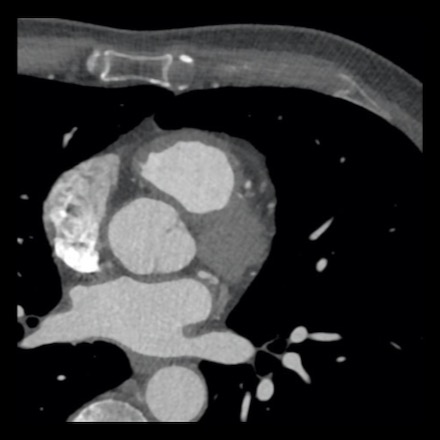

case 1 – CAD-RADS 2/P1

First, scroll through the scan.

Not all images are included. Some images without any abnormalities are skipped

from the series.

How would you describe the findings on the coronary CTA?

The findings are:

- Agatston score of

this patient was 14 (P1). Please, also note the calcification of the aortic valve. - Some partially

calcified and calcified plaques are present in the LAD with mild stenosis

(25-49%). - Calcified-plaque in

the LCX causing minimal stenosis (<25%). - Non-calcified

plaque in the distal RCA causing minimal stenosis (<25%). - This patient classifies

as CAD-RADS 2/P1, which means no further workup is needed.